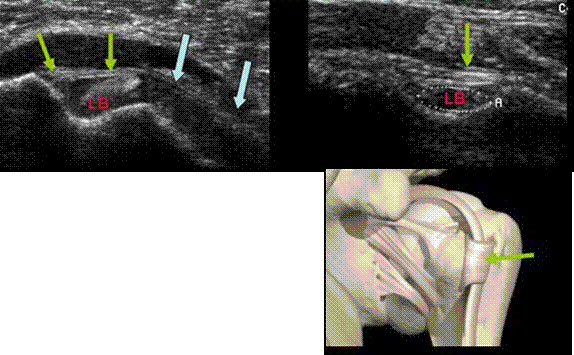

TENOSINOVITA BICEPSULUI

28

FISURA BICEPSULUI(sageata galbena

INGROSAREA TENDONULUI – SAGEATA PORTOCALIE

EPANSAMENT PERITENDINOS-sag.mov

Hipervascularizatie intrea si peritendinoasa